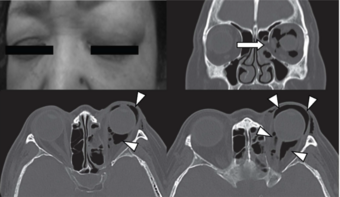

Orbital emphysema.png

Woman with preorbital swelling in orbital emphysema shown in CT scans